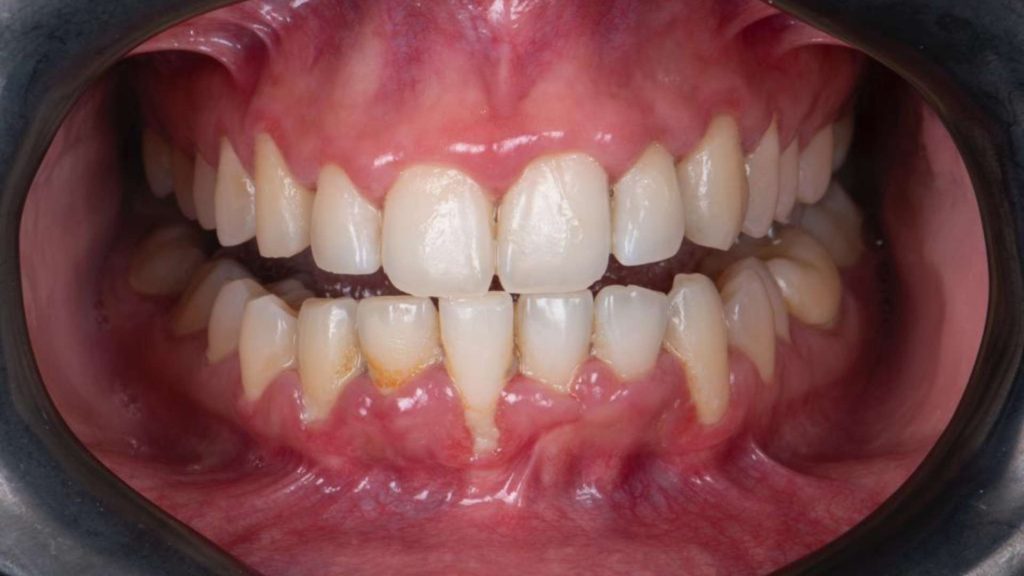

Many cases of periodontal disease progress silently without pain, yet visible signs include localized swelling, gingival redness, bleeding, increasing spaces between teeth, tooth mobility, and frequently, persistent halitosis.

The primary symptom of periodontal disease is bleeding, typically accompanied by gingival swelling and erythema. Patients experiencing these symptoms should immediately consult a periodontal specialist. The specialist will professionally assess disease severity and determine the most appropriate treatment methodology.

Acute periodontal inflammation presents with distinct inflammatory signs around the gingival tissues surrounding teeth: extensive erythema, swelling, purulent discharge, spontaneous bleeding, tooth mobility, and occasionally pain. Interestingly, pain is not typically a prominent feature of periodontal inflammation.